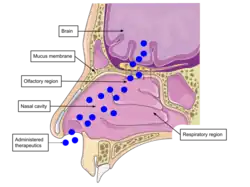

Intranasal delivery pathway

The nasal cavity is highly vascularized, allowing efficient transfer of molecules directly to the nervous system. Compared to other administration routes, nasal drug delivery increases bioavailability and reduces systemic exposure risks. The nasal cavity’s slightly acidic environment and enzymes can affect drug degradation, making delivery systems with neutral to acidic pH ideal. The respiratory region, with its large surface area and high vascularization, is the primary site for drug absorption into systemic circulation. Targeting the olfactory region enhances nose-to-brain drug delivery, as particles can travel via the olfactory nerve to the brain. This route offers potential for treating brain diseases and mental health conditions.[5]